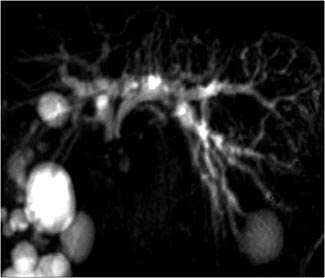

MRCP/PANCREAS - Rhode Island Hospital

MRCP/PANCREAS This protocol is used for evaluation of the biliary tree and pancreas. Indications include pancreatitis, pancreatic mass, biliary ductal dilatation, suspicion of bile duct or gallstones, ... Doc Viewer